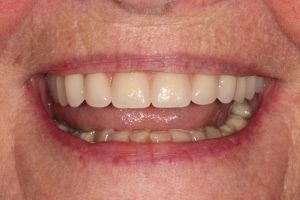

Upper Front Tooth Implant

Both upper front teeth were in a bad way, the upper left one had to be removed as was beyond repair, this was replaced with an implant and a temporary crown on the same day; the upper right front tooth was repaired with a crown. Photos show the result with the definitive crowns after 3 months of treatment.